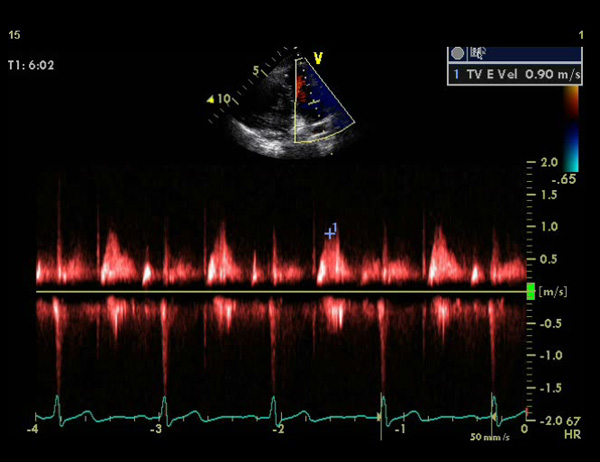

On a normal aorta valve you have three flaps which prevent the blood from leaking back into your heart when it beats. My heart is what they call bicuspid meaning I only have two of the three flaps which leaves a hole; quite a visible hole.

The doctor says that this is congenital, meaning I’ve always had it, I’m only now having some discomfort and other symptoms which caused me to see the cardiologist. From what I’ve read, surgery is the only option to fix this, and the doctor said that I will have a valve replacement in my future.